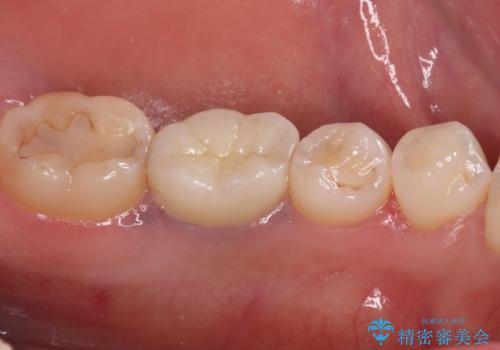

口腔内から、土台も含め銀歯がなくなったことでメタルフリーとなりました。